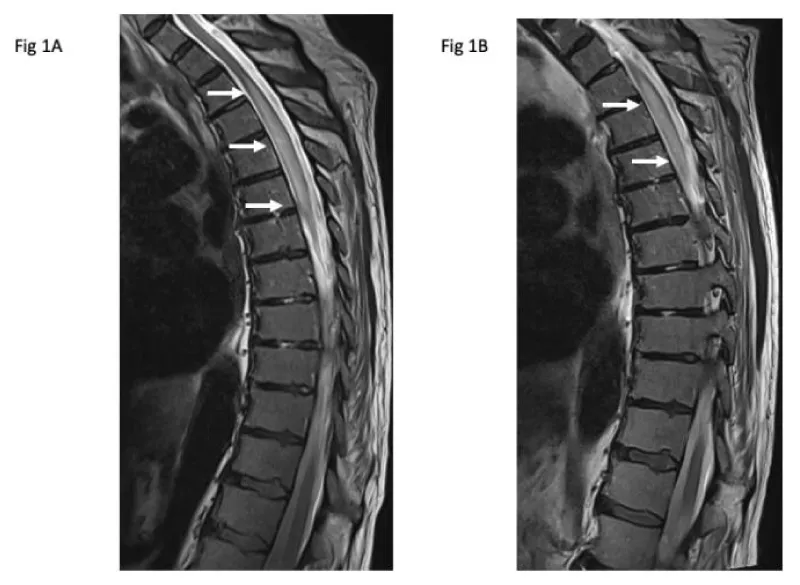

© 2023 Madike R, et al. This is an open-access article distributed under the terms of the Creative Commons Attribution License, which permits unrestricted use, distribution, and reproduction in any medium, provided the original author and source are credited.A 79-year-old man presented with gait dyspraxia approximately 2 days after receiving the first dose of the AstraZeneca COVID-19 vaccine (AZ-COVID-19-vax). He had no previous active issues and was currently on no medications. Physical examination revealed a 4/5 pyramidal weakness of lower limb musculature with loss of sensation up to the inguinal ligament. MRI scan of the spinal cord at presentation demonstrated an abnormal cord signal with gadolinium enhancement extending from T1 to T7, consistent with transverse myelitis (TM) (Figure 1A). CSF protein was elevated with oligoclonal bands detected in both CSF and serum.

There was a recovery of muscle function following intravenous methylprednisolone for 3 days followed by oral prednisolone for 7 days. He was transferred to rehabilitation where he had a relapse, resulting in flaccid paraplegia a week later with a T9 sensory level. An urgent MRI demonstrated an increased cord signal extending between T1 to T7 (Figure 1b). No further recovery occurred despite treatment with intravenous methylprednisolone and plasmapheresis. The patient subsequently passed on due to medical complications of his paraplegia.